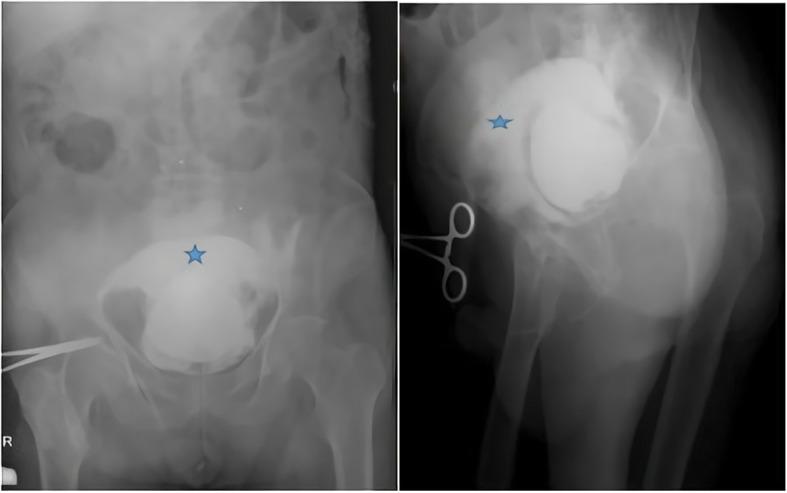

A 77-year-old Caucasian male patient was admitted to the emergency department with abdominal pain, haematuria, and a reduced volume of urine lasting for three days. The patient's amount of urine was reduced, and he came to the hospital for the first time with this complaint. The patient had local bruises on his arms and legs. From the ultrasound, retrograde cystography and computed tomography images, it was thought that there was blood accumulation due to bladder rupture to the intraperitoneal region. Spontaneous bladder rupture secondary to warfarin overdose was considered for this patient who also had an international normalized ratio (INR) level of 13.4. After the INR level was normalized with vitamin K and a prothrombin complex concentrate, the patient underwent surgery. During the operation, a catheter was placed in the bladder, and the bladder mucosa and muscle were closed separately with a primary repair performed by a urologist. The patient was discharged on the 8th postoperative day without any complications.

一名 77 岁的白人男性患者因腹痛、血尿和少尿 3 天入院到急诊科。患者的尿量减少,他第一次因这种症状来医院就诊。患者的手臂和腿部有局部瘀伤。从超声、逆行膀胱造影和计算机断层扫描图像来看,考虑到有血液积聚导致膀胱破裂到腹腔区域。考虑到患者的国际标准化比值(INR)水平为 13.4,因此认为该患者为华法林过量导致的自发性膀胱破裂。INR 水平用维生素 K 和凝血酶原复合物浓缩物正常化后,患者接受了手术。手术中,在膀胱内放置了一根导管,泌尿科医生分别对膀胱黏膜和肌肉进行了一期修复。患者在术后第 8 天没有任何并发症出院。